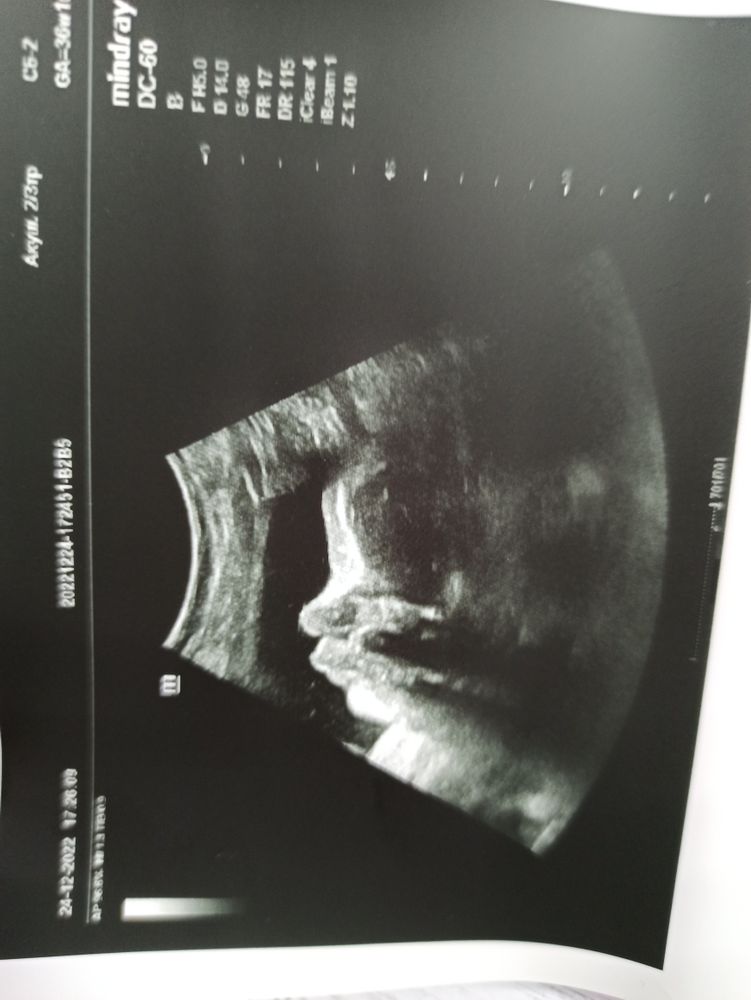

УЗИ почти 37 недель

Шов только после родов оценят. По узи неинформативно . У Вас шейка до этого узи какая была ?

По поводу шва: тут ведь дело и в видении узиста (в каком месте он его померяет и как) и от наполненности мочевого пузыря. Главное, что он у вас без дефектов. Потому что рвется не сам шов, а место соединения с вашей тканью. Мне моя врач ДМН объясняла когда-то.

Шов невозможно оценить на УЗИ, только на МРТ. Если беременность продолжается - с ним все ок.